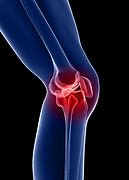

관절염

관절염은 관절에 염증을 일으키는 만성 질환입니다. 골관절염, 류마티스 관절염 및 통풍을 포함하여 무릎 관절에 영향을 줄 수 있는 여러 유형의 관절염이 있습니다. 관절염은 무릎 관절에 통증, 부기 및 뻣뻣함을 유발할 수 있습니다.

반월판 찢어짐

반월판은 무릎 관절을 완충시키는 연골 조각입니다. 찢어진 반월판은 무릎이 갑자기 비틀리거나 회전하는 결과로 발생할 수 있습니다. 이 부상은 운동선수에게 흔히 발생하며 통증, 부기 및 제한된 이동성을 유발할 수 있습니다.